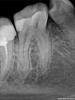

nes84 Опубликовано 30 августа, 2010 Поделиться Опубликовано 30 августа, 2010 здравствуйте, уважаемые стоматологи! я девушка, мне 25 лет, проблемы с десневым карманом 6-ки ( или 7-ки...).сначала думала, что у меня так болит зуб. боль была очень сильная, отдавала в челюсть и язык.сходила к доктору, оказалось это из-за воспаления десневого кармана. карман почистили и промыли. план лечения простой: полоскать Ротоканом, смазывать метрогилом. после заживления ставить коронку тем самым закрыв щель между зубами и сохранив зуб. также возможно придется убрать "нависающую" часть пломбы.доктору доверяю, но зуб болит, характер боли изменился. теперь на холодное реагируют соседние зубы.что делать? ждать? очень страдаю.... Ссылка на комментарий

DokDent Опубликовано 31 августа, 2010 Поделиться Опубликовано 31 августа, 2010 здравствуйте, уважаемые стоматологи! я девушка, мне 25 лет, проблемы с десневым карманом 6-ки ( или 7-ки...).сначала думала, что у меня так болит зуб. боль была очень сильная, отдавала в челюсть и язык.сходила к доктору, оказалось это из-за воспаления десневого кармана. карман почистили и промыли. план лечения простой: полоскать Ротоканом, смазывать метрогилом. после заживления ставить коронку тем самым закрыв щель между зубами и сохранив зуб. также возможно придется убрать "нависающую" часть пломбы.доктору доверяю, но зуб болит, характер боли изменился. теперь на холодное реагируют соседние зубы.что делать? ждать? очень страдаю.... А зачем ждать?Обратитесь к своему доктору,он снимет реакцию зубов на температурные раздражители,обработает Ваш "карман" и сделает всё,что необходимо.Если мало помогает метрогил,попробуйте Холисал-гель.Ошибка многих пациентов в том,что они сидят и ждут " с моря погоды",в надежде,что всё само собой образуется,хотя Ваш доктор может быстро избавить Вас от мучений.Не болейте! Ссылка на комментарий